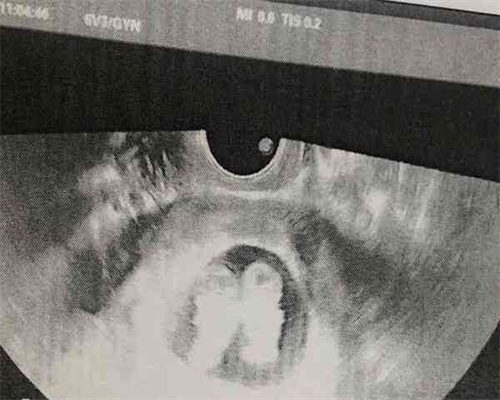

超声腔镜是试管婴儿取卵过程中最关键的工具。它利用超声技术对卵巢进行检查,帮助医生准确解剖、调整深度和大小、确定卵巢的准备程度和卵子的成熟度,并在精确的位置完成取卵。此外,专为超声腔镜设计的腔镜内窥镜配件,如标准定位支架、漏环、手柄等,也是必不可少的配件,可以让专业医生更加轻松、舒适地进行超声腔镜操作。

用于试管婴儿取卵的工具主要是超声手术器械。这种器械主要是通过超声波在卵巢中的精确作用,让外科医生精确定位囊腔所在的空间,然后采取穿刺和取卵的操作,取出卵子,是一种不可替代的卵巢定位手段。取出后,医生还可以对 卵巢 进行清理,使 卵巢 内的器官恢复到正常状态。

试管婴儿取卵术中最重要的部分是使用超声手术器械进行的,它能够精确定位取卵部位。它由一个同轴加针组成,在取卵过程中使用激光源或脉冲组合灯照射囊腔内的组织,使外科医生在手术过程中能够准确地将穿刺孔取到特定深度,从而更准确地取出每一个 卵子。取出 卵子 后,外科医生通过解剖透镜观察,清洗 卵巢 内的组织,然后缝合囊腔,以确保 卵巢 完整无损,并尽量减少患者术后的躯体反应。